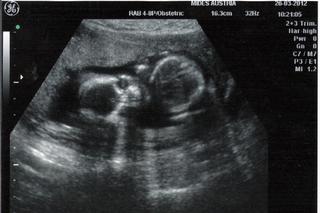

ja som bola v pondelok na poradni a tripltesty vysli v poriadku co som rada aj malicka bola v poriadku a pekne mi mavala🙂 som si zasa foto vypytala tak prikladam...teraz je ullne na opak otocena ako pred mesiacom🙂

za mesiac idem na velky utz a mozem aj manzela zobrat tak ten sa uz tesi...